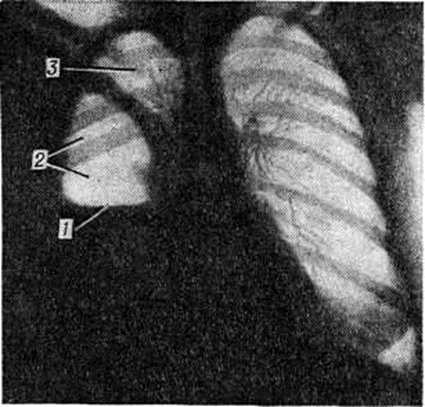

Острое развитие Пиопневмоторакс может обусловить появление симптомов острого живота (напряжение мышц передней брюшной стенки, симптом Щеткина—Блюмберга). При перкуссии лёгких на стороне поражения появляется коробочный звук, при аускультации — ослабление дыхательных шумов, иногда ослабленное бронхиальное дыхание с амфорическим оттенком. При тотальном Пиопневмоторакс с относительно небольшим количеством жидкого гноя иногда возможно определение шума плеска, описанного Гиппократом (смотри полный свод знаний Гиппократа шум плеска). Рентгенологически над горизонтальным уровнем жидкости в плевральной полости виден воздушный пузырь (рисунок 2).